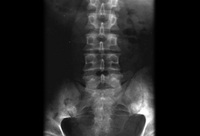

Radiografia simples mostrando sacroileíte bilateral em um paciente com espondilite anquilosante

BMJ 2006;333;581-585. © BMJ Publishing Group Ltd 2009